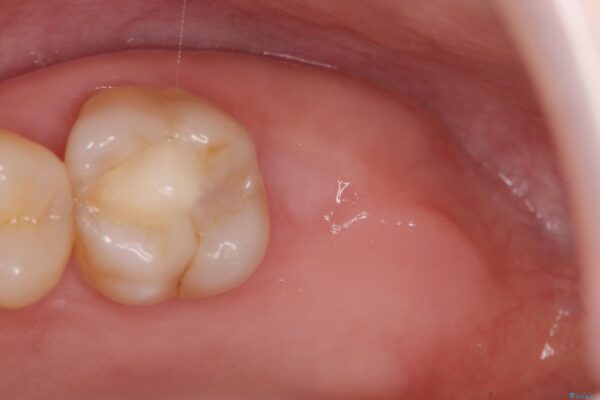

治療前

【噛むと歯が疼く】歯牙破折からのインプラント治療 治療前画像 【噛むと歯が疼く】歯牙破折からのインプラント治療 治療前画像 【噛むと歯が疼く】歯牙破折からのインプラント治療 治療前画像 【噛むと歯が疼く】歯牙破折からのインプラント治療 治療前画像 【噛むと歯が疼く】歯牙破折からのインプラント治療 治療前画像 【噛むと歯が疼く】歯牙破折からのインプラント治療 治療前画像 【噛むと歯が疼く】歯牙破折からのインプラント治療 治療前画像